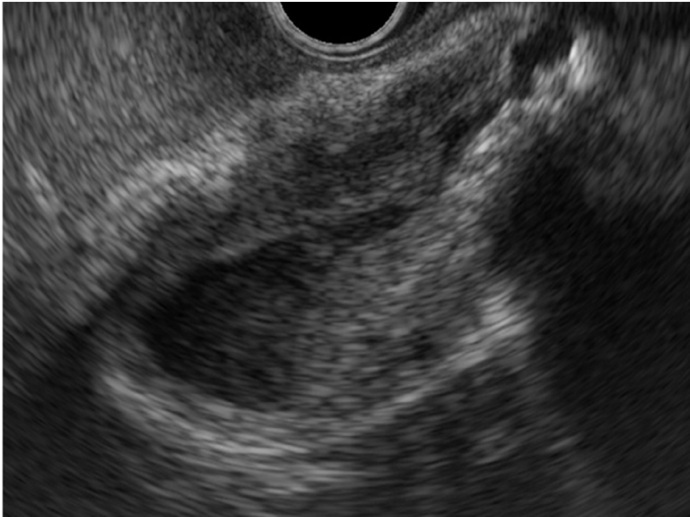

Figura 1 – Neoplasia de vesícula em visão ecoendoscópica. Imagem adaptada de Takahashi et. al. Diagnostics (Basel), 2024.

Forma Infiltrativa (Espessamento da Parede)

- O tumor se apresenta como espessamento focal assimétrico, irregular e heterogêneo da parede da vesícula.

- Pode ser diagnóstico diferencial com patologias benignas como colecistite xantogranulomatosa ou adenomiomatose, mas o EUS ajuda pela visualização das camadas da parede:

- Preservação das camadas → processo inflamatório benigno.

- Desorganização ou perda das camadas → invasão neoplásica.

- A invasão hepática é sugerida por apagamento da interface hiperecogênica entre a vesícula e o fígado.